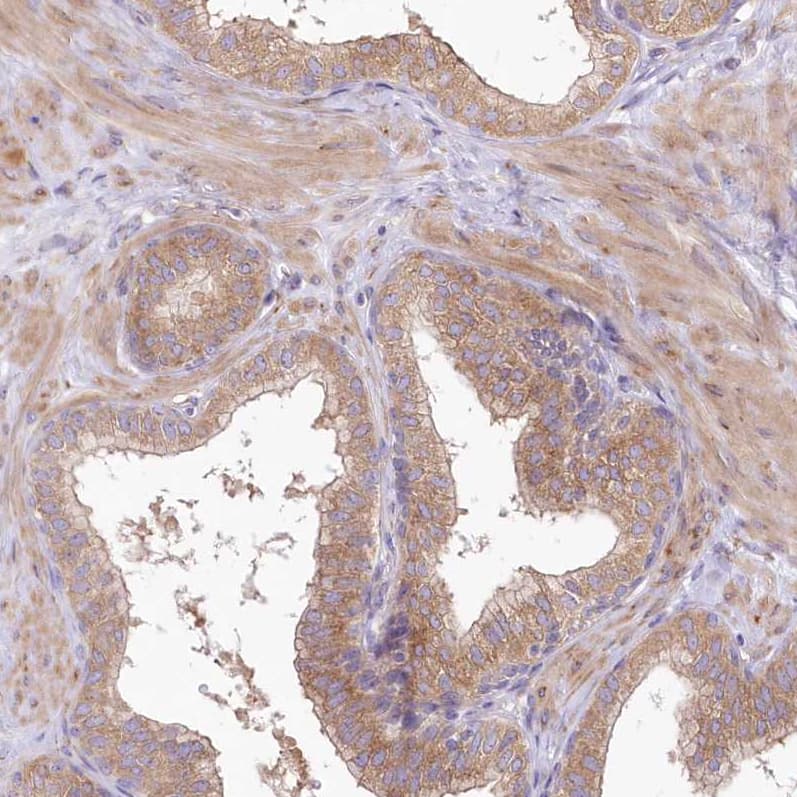

Immunohistochemistry-Paraffin: BIG3 Antibody [NBP1-90759] -Staining of human stomach shows moderate cytoplasmic positivity in glandular cells.

Staining of human prostate shows moderate cytoplasmic/membranous positivity in glandular cells and smooth muscle cells.